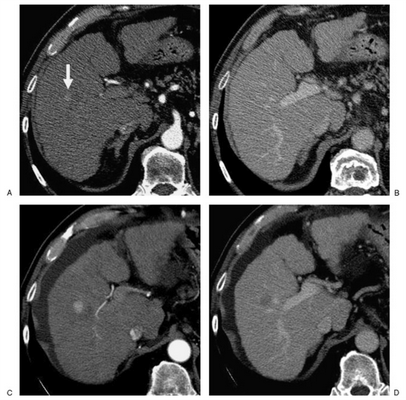

При оценке терапии гепатоцеллюлярной карциномы (ГЦК) следует пользоваться критериями mRECIST вместо RECIST. Оценка проводится при помощи КТ или МРТ, исключительно в артериальную фазу сканирования.

Применение mRECIST при оценке гепатоцеллюлярной карциномы. Оценка таргетного очага применительно только в артериальную фазу при компьютерной томографии (КТ). Согласно критериям RECIST идет подсчет суммы диаметров очагов. В дополнение согласно критериям mREСIST длинник очага оценивается в той части, что наиболее усилилась постконтрастно в артериальную фазу.

На верхних двух изображениях представлены после проведенного лечения (основная опухоль не представлена) первые повторные исследования в артериальной и венозной фазах, при которых выявлен очаг в размерах менее 1 см, что согласно критериям RECIST является не измеряемым. На вторых повторных исследованиях в артериальной и венозной фазах определяется очаг более 1 см с характерными признаками злокачественности (артериальной гиперваскуляризацией и венозным вымыванием), который является теперь измеряемым. В данном случае об прогрессировании заболевания после первого повторного исследования можно говорить только ретроспективно.

Оценка полного ответа:

Отличие от RECIST заключается в том, что все очаги (таргетные, не-таргетные, новые) оцениваются в артериальную фазу контрастирования.